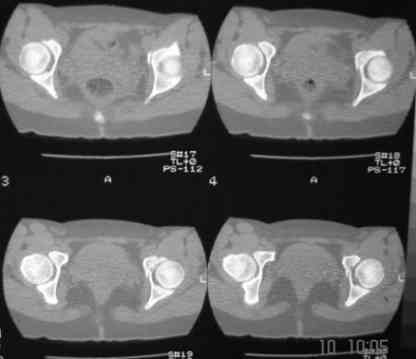

В больнице вправили вывих бедра, три недели на вытяжении. Беспокоят боли в левом тазобедренном суставе и левом крестцово-подвздошном сочленении. Ходит с тростью. Снимок - в приложении. Направил на КТ, заключение: разрыв симфиза и левого крестцово-подвздошного сочленения, переломы крыши и заднего края вертлужной впадины, горизонтальной ветви лонной кости слева.

Уважаемый д-р Булахтин, на мой взгляд единственное повреждение требующее синтеза - застарелый разрыв лона. Низкий перелом передней колонны безопасен, повреждения свода не вижу, неясно что было сзади (скорее боковая масса)лучше сделать обзорный снимок прямой и Inlet.

Очень похоже на повреждение от бокового сжатия.

Если был задний вывих, то повреждение должно локализоваться сзади. В данном случае перелом спереди, как результат сдавления лонного сочленения.

Синтез лонного сочленения восстановит стабильность тазового кольца.

А вывих можно вести не обращая внимания на перелом.

Не наступать на ногу 3 месяца.

АНГБК развивается далеко не у всех, даже после больших реконструктивных операций и в застарелых случаях. Если вывих вправлен в первые 6 часов, шансы на успех вообще больше 90%.

Так, что синтезируйте лоно и ничего не бойтесь.